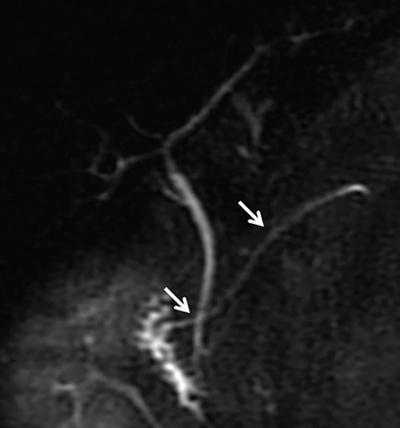

• On MRCP or endoscopic retrograde cholangiopancreatography (ERCP), it manifests as duplication of the major duct in the body or tail of the pancreas.

Image

Axial 3D MRCP image depicting bifid pancreatic duct in body region of pancreas (arrows) with changes of moderate to severe pancreatitis in the tail region (dashed arrow) in the form of dilated side duct branches.